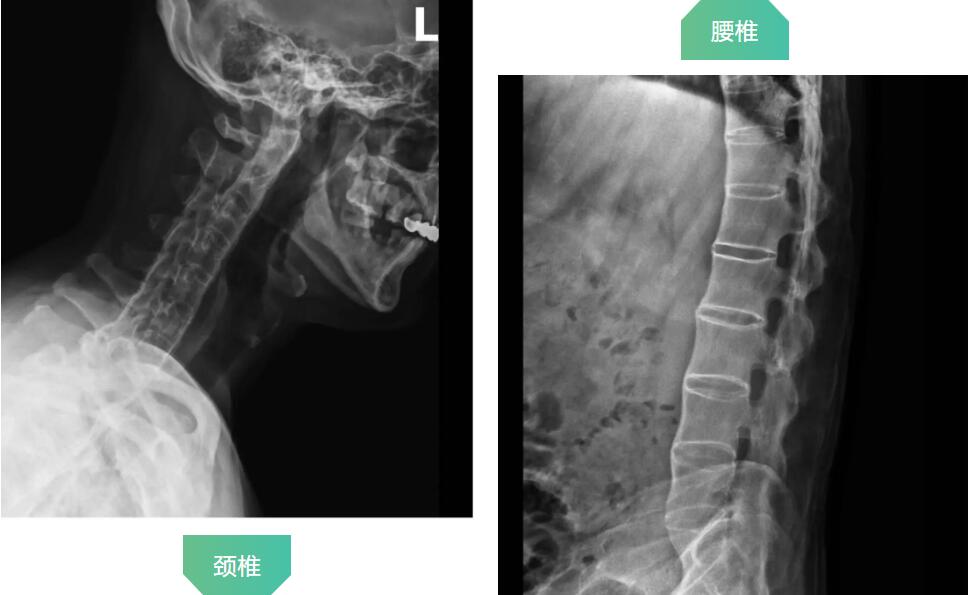

拍片顯示患者頸椎和腰椎已經(jīng)完全融合

羅軍主任分析患者病情,認為他強直性脊柱炎30年,雙髖關節(jié)強直,骨贅增生嚴重,嚴重影響行走功能,診斷為強直性脊柱炎,雙側(cè)髖關節(jié)骨關節(jié)炎晚期。治療方案只有人工髖關節(jié)置換這一種選擇。因患者的頸腰椎已經(jīng)完全融合,手術和麻醉都是一個不小的挑戰(zhàn),羅軍主任帶領關節(jié)置換團隊協(xié)同麻醉科團隊,經(jīng)過嚴密細致的討論,與患者及家屬充分溝通交流后,決定行機器人輔助DAA入路全髖關節(jié)置換術。機器人輔助加微創(chuàng)置換,為這項高難度手術提供了有力支撐。